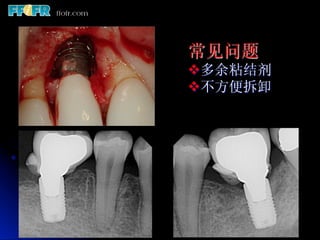

常见问题

v 多余粘结剂

v 不方便拆卸